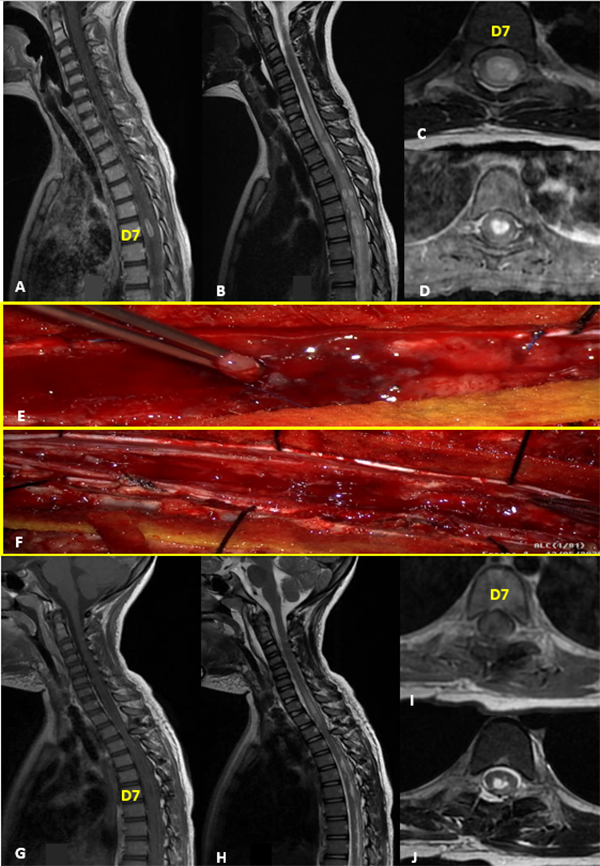

II: Indeterminado

Figura 2:

Indeterminado. A-D: RM prequirúrgica T1 con contraste y T2 cortes axiales y sagitales. E-F: Ecografía intraoperatoria. G: Imagen intraoperatoria. H-K: RM postquirúrgica T1 con contraste y T2 cortes axiales y sagitales.